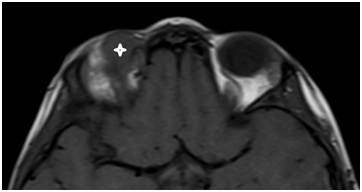

Figure 2a T1 axial MRI of the mass.

Figure 2b T1 coronar MRI with contrast of the mass.

Orbital MRI revealed a well-circumscribed mass lesion which is located extraconal, superior part of right orbit and behind the medial canthus, isointense with respect to brain parenchym on T1 and T2A, showed diffuse homogeneous contrast enhancement after intravenous injection of contrast. Lesion’s approximate size was 22x16x10 mm and pushing the eyeball and superior rectus muscle inferiorly. The mass caused to erosion in frontal bone. WBC: 17.690/dL, RBC: RBC: 1.55K/dL, Hgb: 4.6g/dL, Htc: 14g/L, Plt: 49K/dL were in complete blood account. Lactate dehydrogenase was 831U/L in biochemical examination. Peripheral blood showed an increased total leucocyte count (17,000cells/mm3). Her differential leucocyte count revealed 5% neutrophils, 12% lymphocytes, 2% eosinophils, 2% monocytes, 79% myeloblasts and immature myeloid precursors which included promyelocytes, myelocytes and metamyelocytes. Patient was t (8;21) positive and the subtype was AML M2. The bone marrow aspirate showed hyper cellular marrow smears with replacement of haemopoietic cells by blasts and blasts were Sudan Black B positive. Patient referred to paediatric haematology clinic and treated with standart cytarabine and anthracycline based chemotherapy protocole and re-evaluated at the end of the 2nd week of the treatment. Blasts were decreased to 15% and proptosis disappeared in examination. And the blasts decreased below to 5% at the end of 4th week and the choloma disappeared in the orbital MRI.